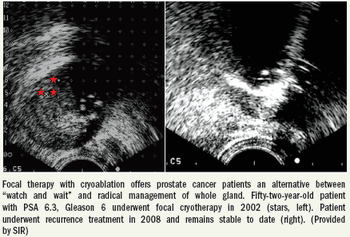

More than a decade's worth of data suggest cryoablation can treat localized malignancies within the prostate more safely and effectively than do the standard treatment approaches that are generally applied to the whole gland.